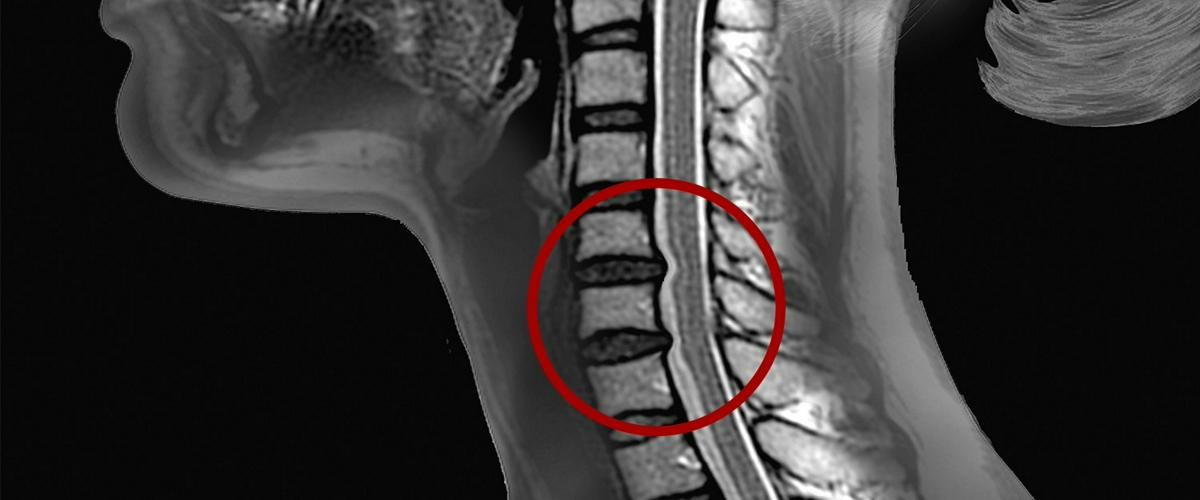

Известно, что иммунные клетки проникают в место повреждения спинного мозга и активируют защитные воспалительные реакции. Теперь ученые установили, что пик притока клеток происходит с 7 до 14 день после травмы. При этом травма немедленно ухудшает функцию клеток, защищающих спинной мозг.

Сравнивая различия в травмах у молодых и старых грызунов, ученые обнаружили сниженную активность астроцитов у последних. Обычно астроциты быстро реагируют на повреждение и образуют защитные границы вокруг участков повреждений. Также у старых мышей наблюдалась повышенная гибель нейронов и иммунная активность. Как следствие, у них было больше функциональных нарушений и рисков развития паралича.